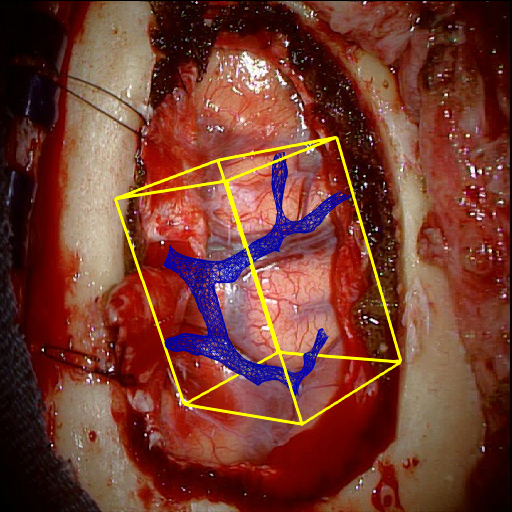

Fig. 5 shows our results as Augmented Reality views with bounding boxes and overlaid meshes. Our method produced visually consistent alignments for all 6 clinical cases without the need for initial registration. Because our current method does not account for brain-shift deformation, our method produced some misalignment errors. However, in all cases, our predictions are similar to the ground truth.